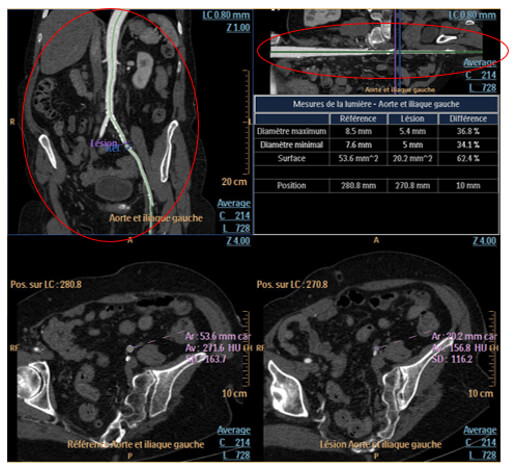

Stenosis Measurement

For stenosis quantification, you have to place the reference on the curvilinear or the stretched vessel image. Once positioned, verify the vessel’s contour for the reference and the lesion.

Stenosis Percentages

Stenosis percentages, maximum and minimum diameter and the surface are displayed in the following table.